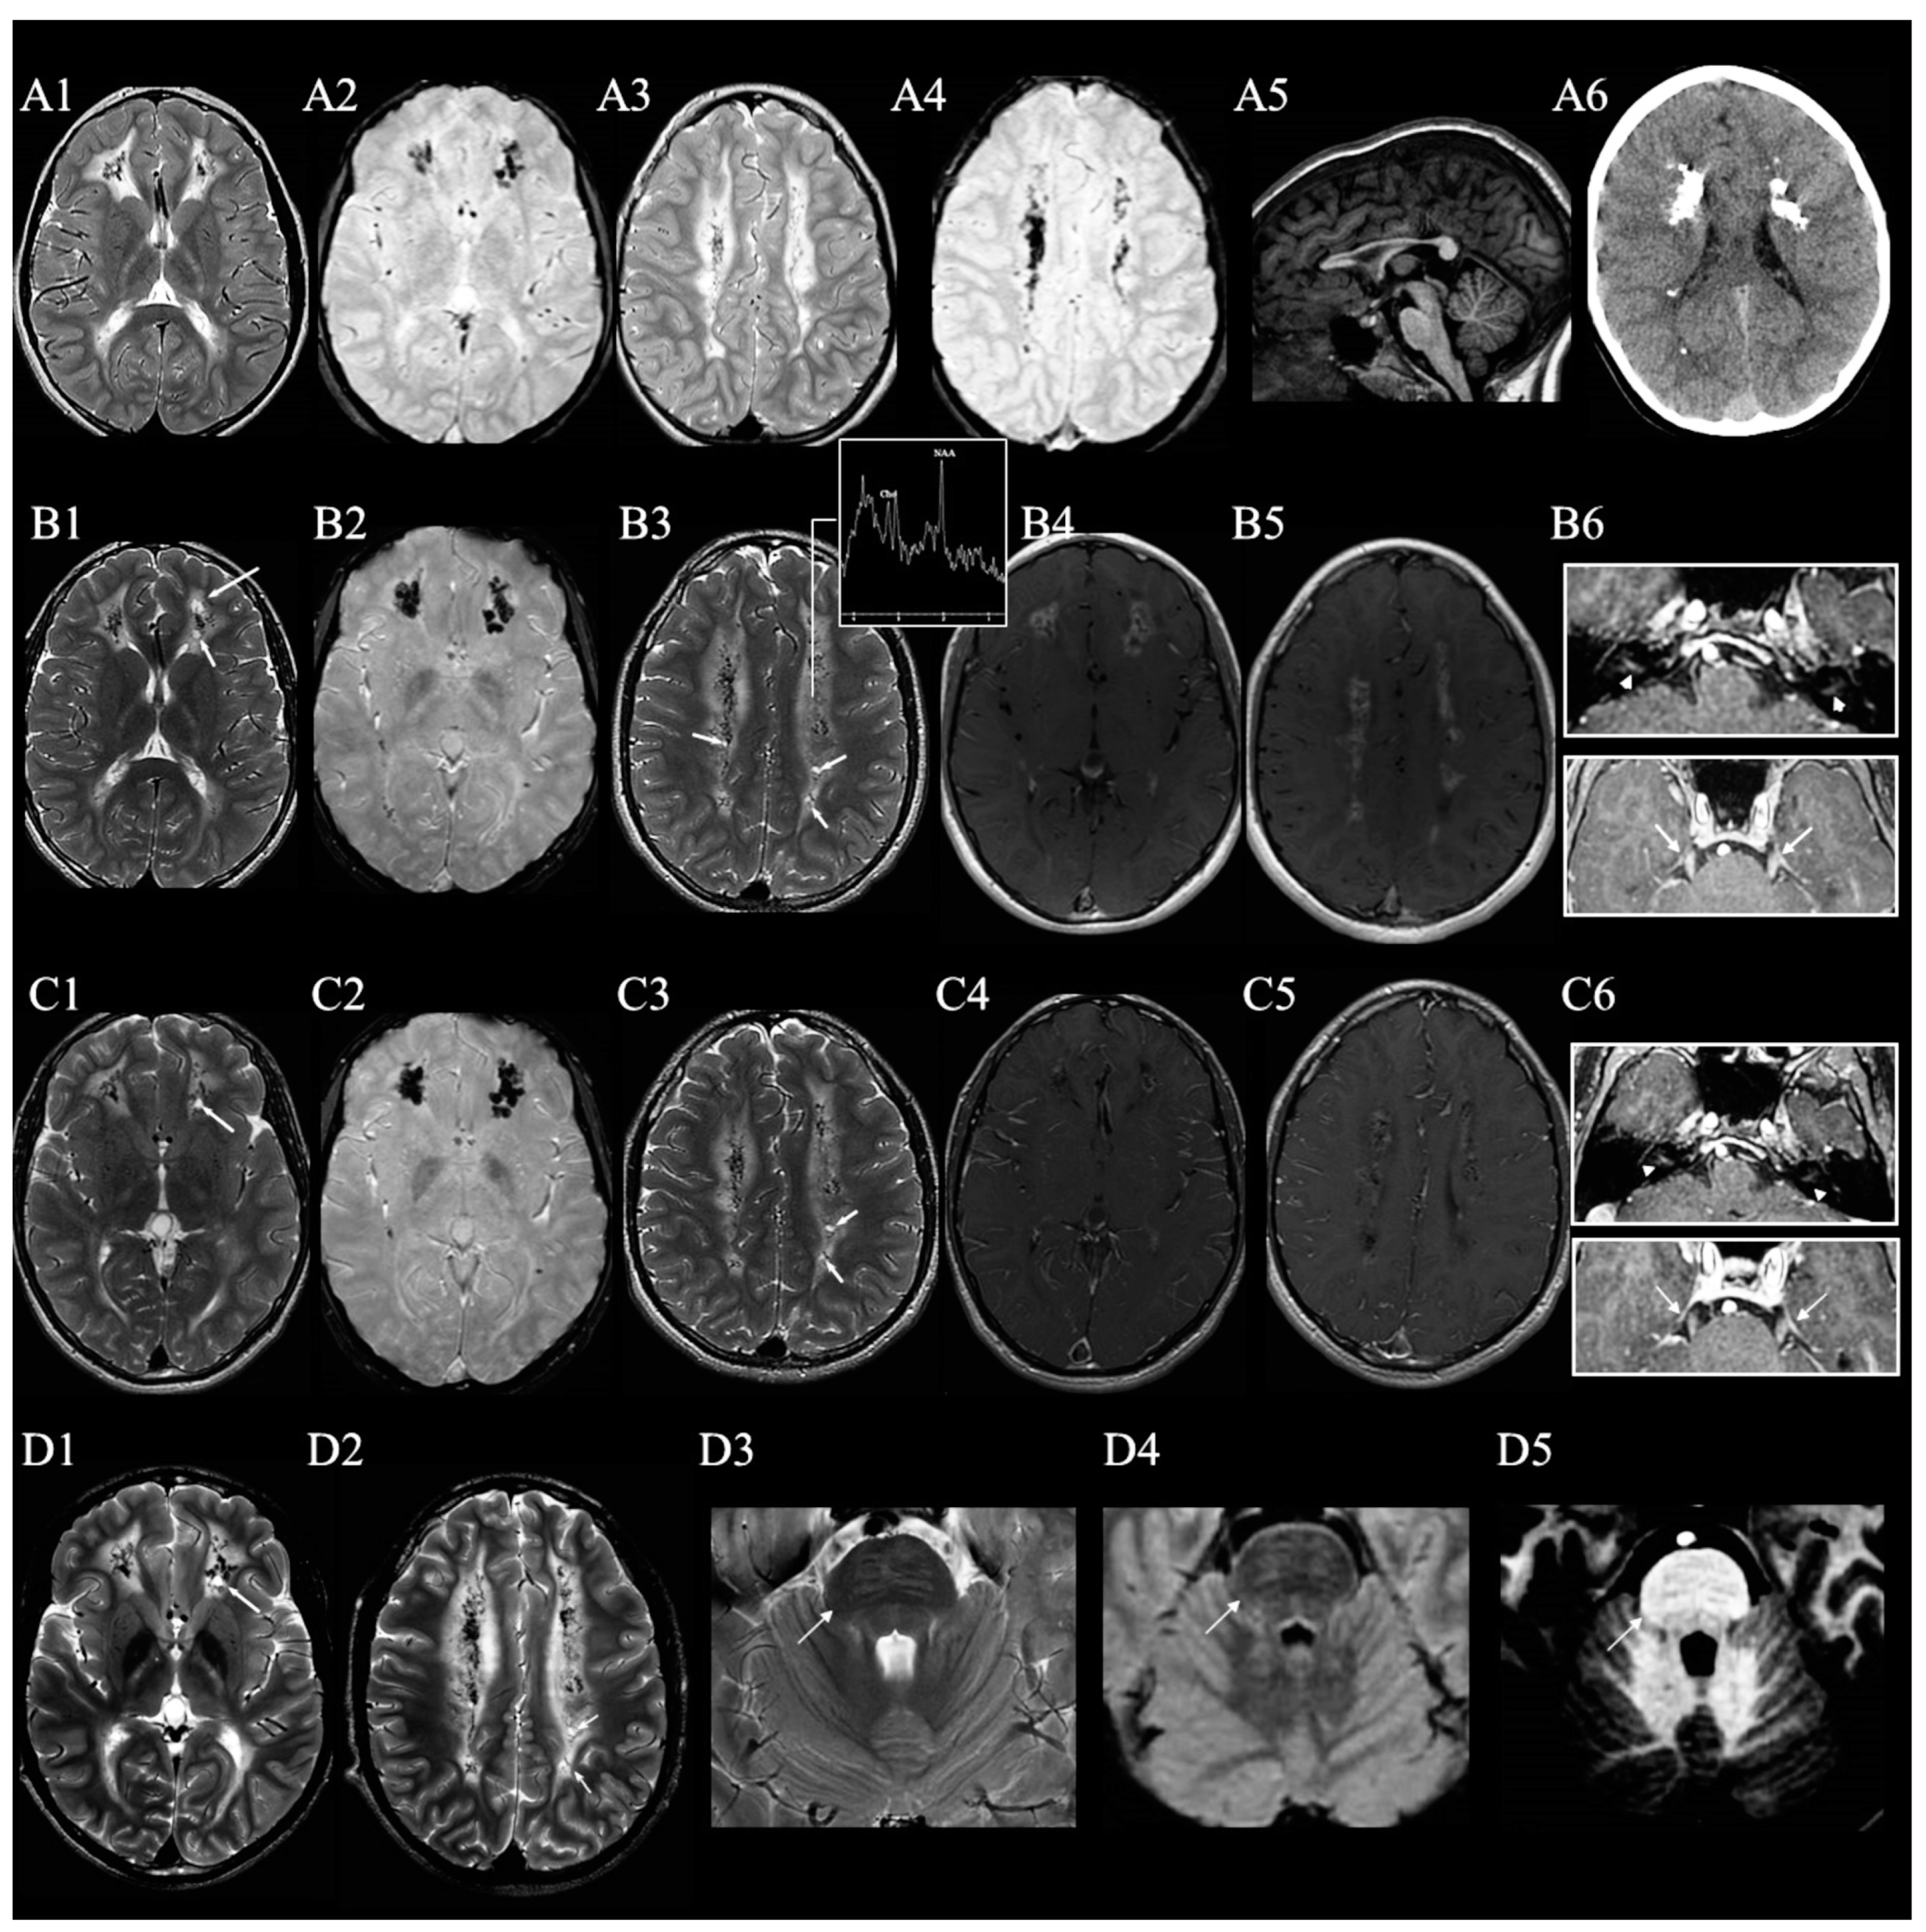

| This study | 6 yr | 16 yr | N | 6 yr | Spastic-paraparesis, bradykinesia, ataxia, sensorimotor neuropathy, intellectual disability | Hyperactivity in preschool, anxiety, depressed mood and repetitive behaviors | Strabismus and probable HD | c.4788_4799dup, p.Ser1597_Leu1600dup | VUS |

| Nicita et al. [15] | 1 mo | 2 yr | Y | NAIA | Poor cognitive and motor development, truncal hypotonia, appendicular spasticity, exaggerated startle response, fever-induced focal motor seizures from 9 months | None | Congenital macrocephaly, ureteropelvic junction stenosis | c.4811 T > G, p.(Val1604Gly) | LP |

| Helman et al. [4] | 1 yr | 25 * | Y | 2 yr, wheelchair at 6 yr | Intellectual impairment, spasticity, ataxia and peripheral neuropathy | Cognitive decline, neuropsychiatric symptoms with passive disposition, lack of movement and communication and mood fluctuations | Hypogonadotropic hypogonadism | c.4814_4819dupTCTTCA p.(Phe1606_Lys1607insIlePhe) | LP |

| 15 yr | 37 * | N | 20 yr, wheelchair at 25 yr | Appendicular ataxia, severe spasticity, pseudobulbar dysarthria, peripheral neuropathy | Cognitive decline | Type 2 Diabetes | c.5046C > G p.(Asn1682Lys) | LP | |

| 40 yr | 65 yr | N | 40 yr | Bilateral leg weakness, spasticity, imbalance | Depression and cognitive decline | Episode of myelitis treated with steroids in adolescence | c.4583G > A p.(Cys1528Tyr) | LP | |

| 1 yr | 28 yr | Y | 1 yr, wheelchair at 16 yr | Lost speech, spasticity, dystonic foot posturing, painful muscle spasms | Depression, temper issues, periods of aggression, inappropriate laughing and crying | Staring spells but no epileptic EEG activity | c.5046_5047delCCInsAG p.(Asn1682_Arg1683insLysGly) | P | |

| 0 yr | 9 yr | Y | 5 yr, wheelchair at 9 yr | Intellectual disability, spasticity, global muscle wasting | No | HD, short stature | c.5042A > G p.(Asp1681Gly) | P | |

| 0 yr | 6 yr | Y | NAIA | Intellectual disability, truncal hypotonia, limited head control, appendicular spasticity, dystonic movements | No | HD, atrial septal defect, glabellar hemangioma, microcephaly, short stature | c.5078T > C p.(Phe1693Ser) | P | |

| 0 yr | 6 yr | Y | NAIA | Intellectual disability, generalised hypotonia, myoclonic seizures | No | No | c.4754T > C p.(Leu1585Pro) | P |